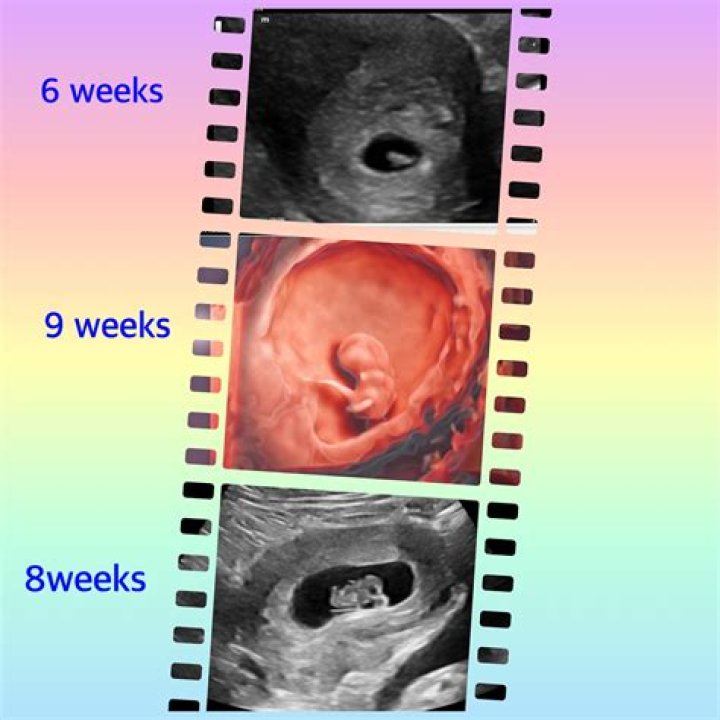

What Do Pictures of Miscarriages at 6 Weeks Show?

Pictures of miscarriages at 6 weeks often depict small clots of tissue or embryonic material. These images can help individuals understand the physical process of miscarriage and what to expect. However, they should be viewed with care, as they may be distressing for some people.

While discussing pictures of miscarriages at 6 weeks, it’s important to approach the topic with sensitivity. These images are not intended to alarm or upset but to provide clarity and understanding. They often show the following:

• Small clots of tissue resembling blood or mucus

• Embryonic material that may be difficult to identify without medical expertise

• Signs of uterine lining shedding

Viewing these images can help individuals recognize what they may experience during a miscarriage. However, it’s essential to remember that every miscarriage is unique, and not all cases will look the same.